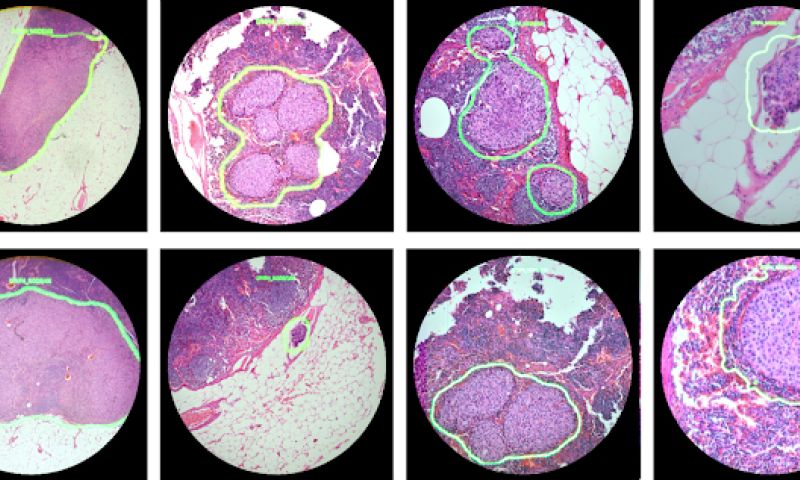

Door de lens van de microscoop heen ziet de onderzoeker dan meteen een kringetje of een heatmap rondom het zieke gedeelte. De AR-microscoop geeft de meldingen door met een snelheid van 100 milliseconde, dus zo goed als real-time.

De Google-onderzoekers hebben de microscoop nu getraind op borst- en prostaatkanker, maar volgens hen kan de technologie gemakkelijk uitgebreid worden naar andere ziektes, zoals malaria en tbc. Ook is het volgens hen mogelijk om de technologie toe te passen op bestaande microscopen.